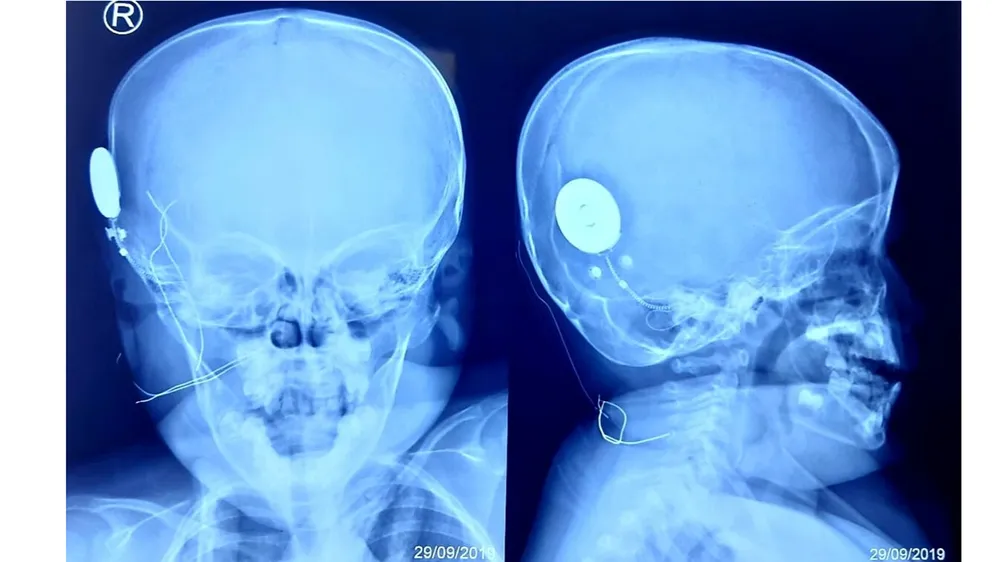

Mang lại âm thanh cho bé gái 40 tháng tuổi bị điếc bẩm sinh ảnh 1 Hình ảnh chiếc tai điện tử sau khi được cấy vào ốc tai bệnh nhi. Ảnh: BVCC

Theo bác sĩ CK2 Bạch Thiên Phương, Trưởng khoa Tai mũi họng BV Nhi Đồng TP, ca phẫu thuật được thực hiện trong 2 giờ. Sau khi đặt điện cực ốc tai, các chỉ số kiểm tra hoạt động của tất cả các điện cực bằng cách đo trở kháng và trường (Impedence and Field Telemetry IFT) và đo đáp ứng thần kinh hạch xoắn ốc tai ART (Audio nerver Respond Telemetry) đều rất tốt.